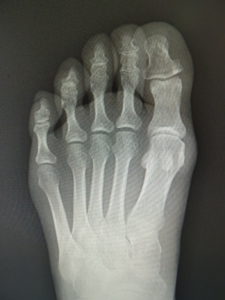

おおむね、外反角が30度以上になると、保存治療はもはやあまり有効ではありません。症状が強く、患者さんと良く吟味の上、希望されれば手術へと進みます。他に根治療法はないが、手術なら根治できます(図5)。ただMP関節の変性性変化があると、痛みや拘縮が残ることがあります。

(図5)

手術前 手術後4年

(図6)

手術前 手術後

(図7)

真田理事長による手術の様子。外反母趾|症例 (左から 手術前、手術後、ワイヤ抜去後)